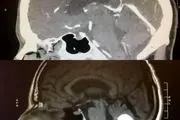

• غیب شدن عجیب و ناگهانی تومور مغزی یک روز قبل از عمل! + عکس

غیب شدن عجیب و ناگهانی تومور مغزی یک روز قبل از عمل! + عکس

تومور مغزی یکی از عوامل مخرب و غیر طبیعی ای است که به دلیل رشد و فعالیت برخی سلول ها ممکن است به وجود آید و بیمار برای درمان، باید تحت جراحی پزشکان قرار بگیرد!

۱۱ شهریور ۱۴۰۰